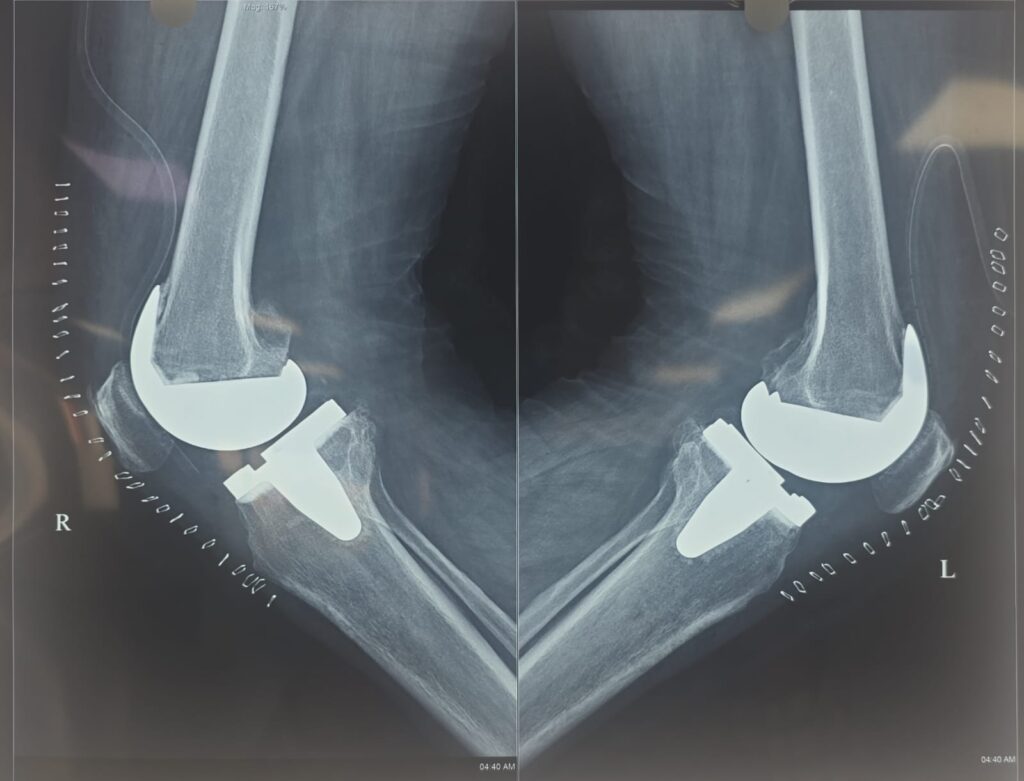

Joint Replacement

Advanced surgical care to replace damaged joints, relieving pain and restoring mobility with modern, minimally invasive and robotic techniques.